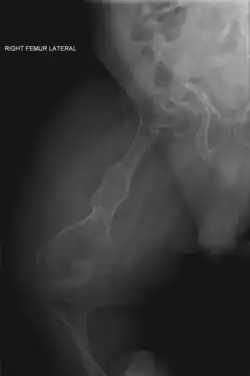

| II | Enfermedad de Vrolik, autosómica recesiva. Se caracteriza por fragilidad ósea extraordinaria, culmina en la muerte en el periodo perinatal o comienzos de la lactancia, huesos largos muy fragmentados (fémur en acordeón), prominencia de hueso parietal y temporal con occipucio colgante y osificación de cráneo retrasada extraordinariamente. |

| VII | Se parece a los tipos V i II. Tala baja y acortamiento de extremidades. Es un tipo de OI recesivo que se debe a una mutación en el gen CRTAP. |

| VIII | Se parece a los tipos II y III. Grave deficiencia de crecimiento y extrema desmineralización del esqueleto. OI recesiva debida a una mutación en el gen LEPRE1. |

_of_right_femur.png)